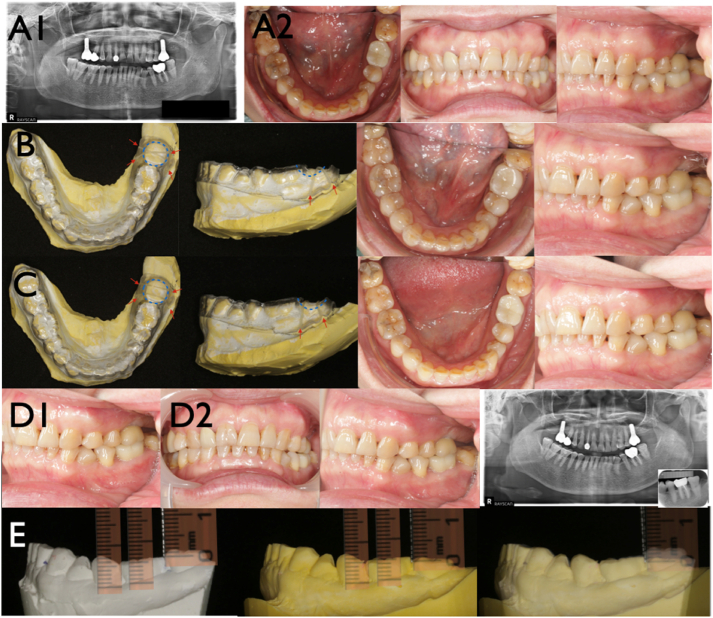

Efficacy of clear retainers on intrusion of mandibular molar without skeletal anchorage.

透明固位器对下颌磨牙无骨支抗侵入的疗效观察。